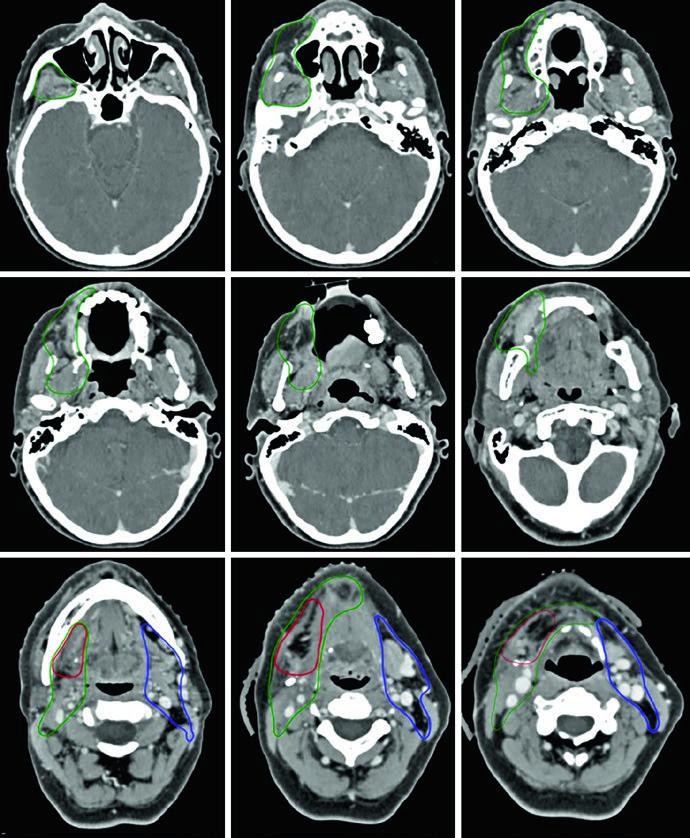

Caso Clínico: Carcinoma de Língua Oral T3N2b

A Figura 6.1 ilustra um paciente com carcinoma espinocelular (CEC) de língua oral, estadiamento patológico T3N2b, pós-glossectomia parcial com margens cirúrgicas microscopicamente positivas. O CTV66 (vermelho) cobre a região da margem positiva. O CTV60 (verde) abrange o leito cirúrgico completo, e o CTV54 (azul) inclui os níveis linfonodais cervicais.

No lado ipsilateral, níveis I a V são incluídos. No contralateral sem doença, níveis I a IV. A cobertura do nível V é recomendada para tumores primários de língua oral, especialmente após manipulação cirúrgica do pescoço e na presença de doença nodal ipsilateral. O nível IA deve ser coberto sistematicamente em tumores de língua oral.

Quando há preocupação com envolvimento de tecidos moles superficiais, bolus e flash são recomendados. O espaço retroestilóideo ipsilateral é zona de risco para metástase nodal, particularmente quando há comprometimento do nível II. Os linfonodos retrofaríngeos apresentam baixo risco e geralmente não são incluídos. A cobertura do nível VI é fortemente recomendada em pacientes com doença nodal positiva.